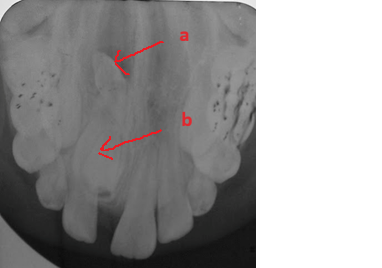

Răng thừa (b) mọc trong vòm miệng khiến cho R22 (a) mọc lệch xoay trục XQ răng toàn cảnh không thấy răng thừa do R21 (a) che khuất,(b) là R22 bị xoay trục

Hình ảnh răng thừa (a) xuất hiện rất rõ trên CT Cone Beam, (b) là hình ảnh R21

Hình 3: Tính ưu việt của CT Cone Beam trong chẩn đoán răng thừa

(Nguồn: Bệnh viện Đa khoa Tỉnh Quảng Trị)